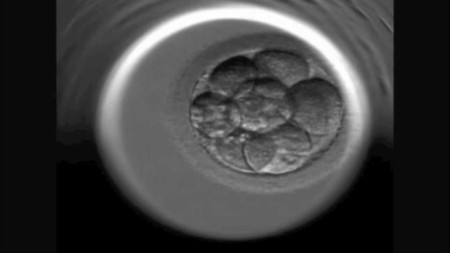

En el vídeo podéis ver las complejas divisiones celulares que se dan desde la unión del óvulo y el espermatozoide y la formación del cigoto (primera célula fecundada) hasta la creación de la mórula, llamada así porque se asemeja a una mora. En los humanos llega a estar formada hasta por 32 blastómeros a los cuatro días de la fecundación.